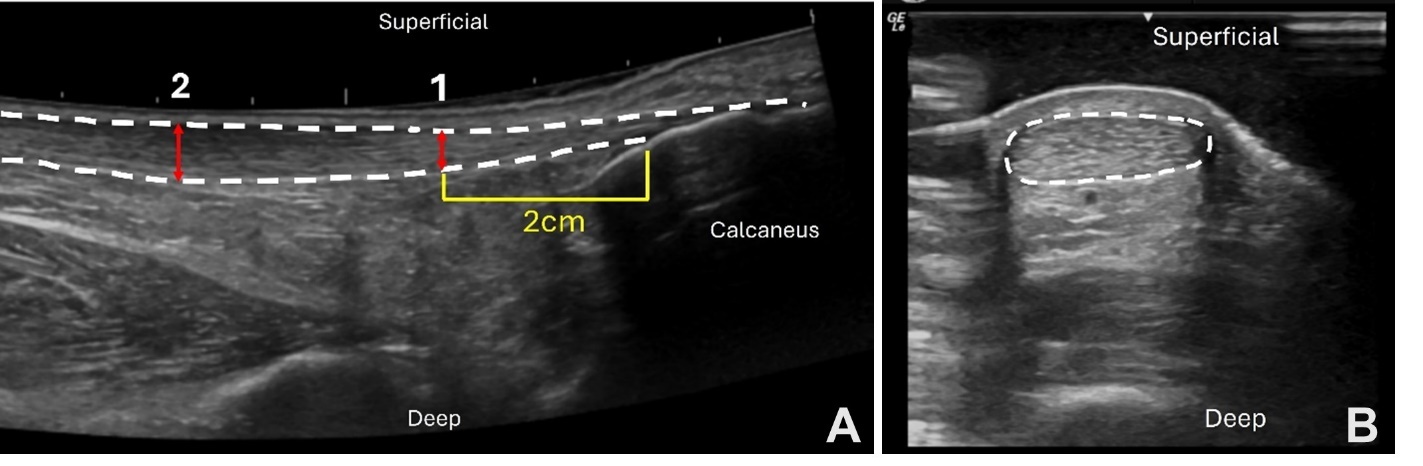

The detailed methods utilized to assess the following tendon structure variables have been previously described.20 Ultrasound imaging (GE LOGIQ e; GE Healthcare, Chicago, Illinois) was performed using the B-mode ultrasound and a 5cm linear array transducer set to a frequency of 10Hz and a depth of 3.5cm. Achilles tendon thickness (mm) was assessed as the area of maximal anterior to posterior tendon thickness per visualization upon ultrasound imaging. The degree of Achilles tendon thickening (mm) is a measure of Achilles tendon pathology.6 This was assessed by subtracting the thickness of healthy Achilles tendon at 2cm (or an adjusted location if thickening was present at 2cm) from the maximal tendon thickening (Figure 2a). Achilles tendon cross-sectional area (CSA, mm2) was measured with the ultrasound probe in short axis using a gel-standoff pad to increase visibility of the Achilles tendon (Figure 2b). CSA was measured at the marked location for maximal tendon thickness. Images were exported and measured (Osirix Dicom Viewer; Pixmeo SAL, Bernex, Switzerland) and the mean of three images was used for analysis.